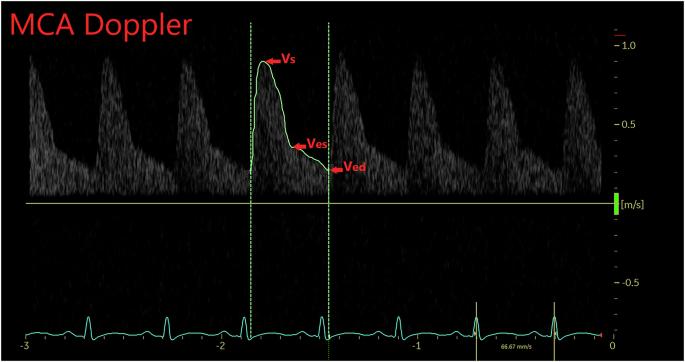

The relationship between systemic hemodynamics and cerebral perfusion in neonates, particularly those with systemic hypotension, is complex and not clearly elucidated. Targeted neonatal echocardiography (TNE) provides valuable insights into cerebral hemodynamics by quantifying middle cerebral artery (MCA) flow in the context of systemic hemodynamics. To investigate the correlation between blood pressure (BP), cardiac output (CO), and MCA Doppler indices in neonates, hypothesizing that BP alone is not a reliable measure of cerebral perfusion. A retrospective cohort study of neonates who underwent their first TNE in the Neonatal Intensive Care Unit. The analysis focused on the relationship between BP components and MCA Doppler measures (i.e., resistive index and pulsatility index). The study included 194 neonates born at a mean gestational age and weight of 30.7 ± 6 weeks and 1744 ± 1246 g, respectively, classified into normotensive, hypotensive, and normotensive-treated groups. Weak correlations were observed between MCA Doppler measures and BP components across the entire cohort. Group comparisons found that neonates in the hypotensive group exhibited higher MCA-RI compared to both normotensive and normotensive-treated groups. Exploratory analyses revealed significant variation in MCA-RI that was explained by cardiac output after accounting for BP and gestational age. These findings suggest that BP alone is not a sufficient indicator of cerebral perfusion status. While the correlations were expected to be weak given the dynamic nature of cardiac output, the results highlight the need for comprehensive hemodynamic assessments in neonates with cardiovascular compromise to avoid reliance on oversimplified metrics such as BP versus Dopplers.

Abstract Image